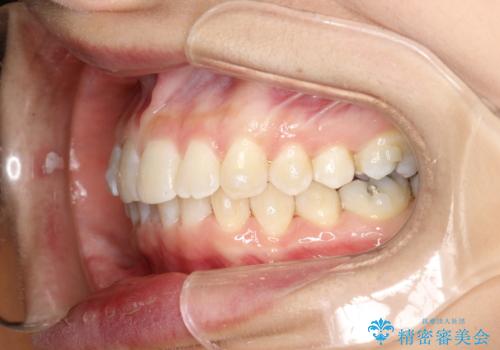

- 前歯のがたつきを気にされて来院されました。

右上の前から2番目の歯が前方に大きく傾いており、下の前歯もガタガタしていました。

インビザラインにて、歯と歯のあいだをわずかに削り並べる計画としました。

しっかりとマウスピースを使用していただけたので、順調に治療を終えることができました